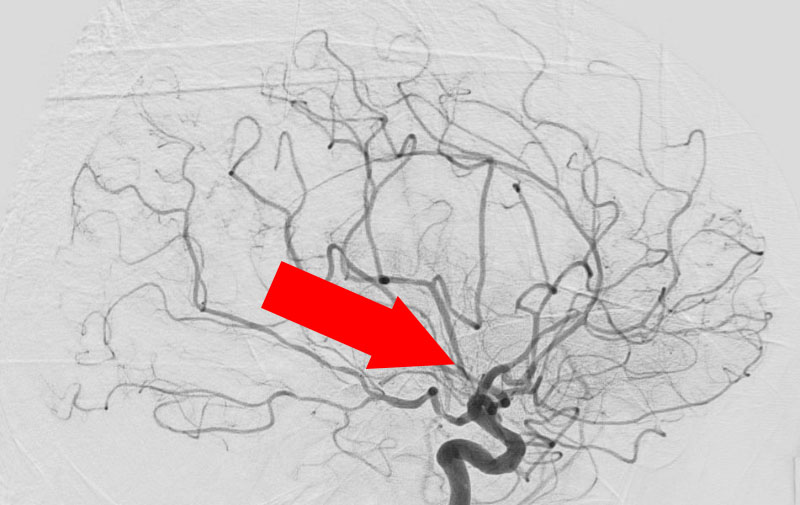

'21年12月

脳動静脈奇形

70代

院内外来

No.1159 手術前

No.1159 手術中

No.1159 手術後